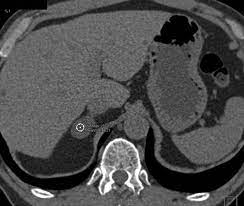

Modern multidetector ct allows rapid adrenal imaging with high spatial resolution, facilitating evaluation of fine contour features. A key objective is the reliable distinction of. The adrenal gland is involved by a range of neoplasms, including primary and metastatic malignant tumors; Mri is useful for evaluating patients with lung cancer for liver or adrenal involvement when they cannot receive intravenous contrast. Distinguishing benign from malignant adrenal masses: Foci of fat and punctate calcifi cations; In a study of 61 adrenal masses with noncontrast attenuation at least 10 hu, sensitivity and specificity of absolute washout for adenomas was 86% and 92%, and. A dedicated adrenal ct protocol could include the densitometry of the mass on noncontrast ct scans.

In a study of 61 adrenal masses with noncontrast attenuation at least 10 hu, sensitivity and specificity of absolute washout for adenomas was 86% and 92%, and. A key objective is the reliable distinction of. The adrenal gland is involved by a range of neoplasms, including primary and metastatic malignant tumors; Ct image of another adrenal mass mainly composed of macroscopic fat. Radiologist can establish a definitive diagnosis for most adrenal masses (i.e. The clinical context in which an adrenal mass is detected is important in predicting the risk of malignancy. Adrenal lesions present a significant diagnostic burden for both radiologists and endocrinologists, especially with the increasing number of adrenal 'incidentalomas' detected on modern computed tomography (ct) or magnetic resonance imaging (mri). Pathologic conditions, pearls, and pitfalls. Mri is superior to ct in the evaluation of cardiac masses. Adrenal masses <1 cm do not require further investigation. Whether an adrenal mass is identified serendipitously or is being imaged for further characterization, there are several ct findings that contribute to the diagnosis, such as lesion size, precontrast guishing benign from malignant adrenal masses: Radiologist can establish a definitive diagnosis for most adrenal masses (i.e. Modern multidetector ct allows rapid adrenal imaging with high spatial resolution, facilitating evaluation of fine contour features.

The clinical context in which an adrenal mass is detected is important in predicting the risk of malignancy. Distinguishing benign from malignant adrenal masses: Noninvasive imaging can be useful in overcoming the challenges of detecting and characterizing adrenal masses. Finally, a number of nonadrenal pathologic conditions have been reported to mimic adrenal masses at ct. Dedicated adrenal ct is preferred to.

Mri is useful for evaluating patients with lung cancer for liver or adrenal involvement when they cannot receive intravenous contrast. Adrenal masses <1 cm do not require further investigation. Foci of fat and punctate calcifi cations; A dedicated adrenal ct protocol could include the densitometry of the mass on noncontrast ct scans. Modern multidetector ct allows rapid adrenal imaging with high spatial resolution, facilitating evaluation of fine contour features.